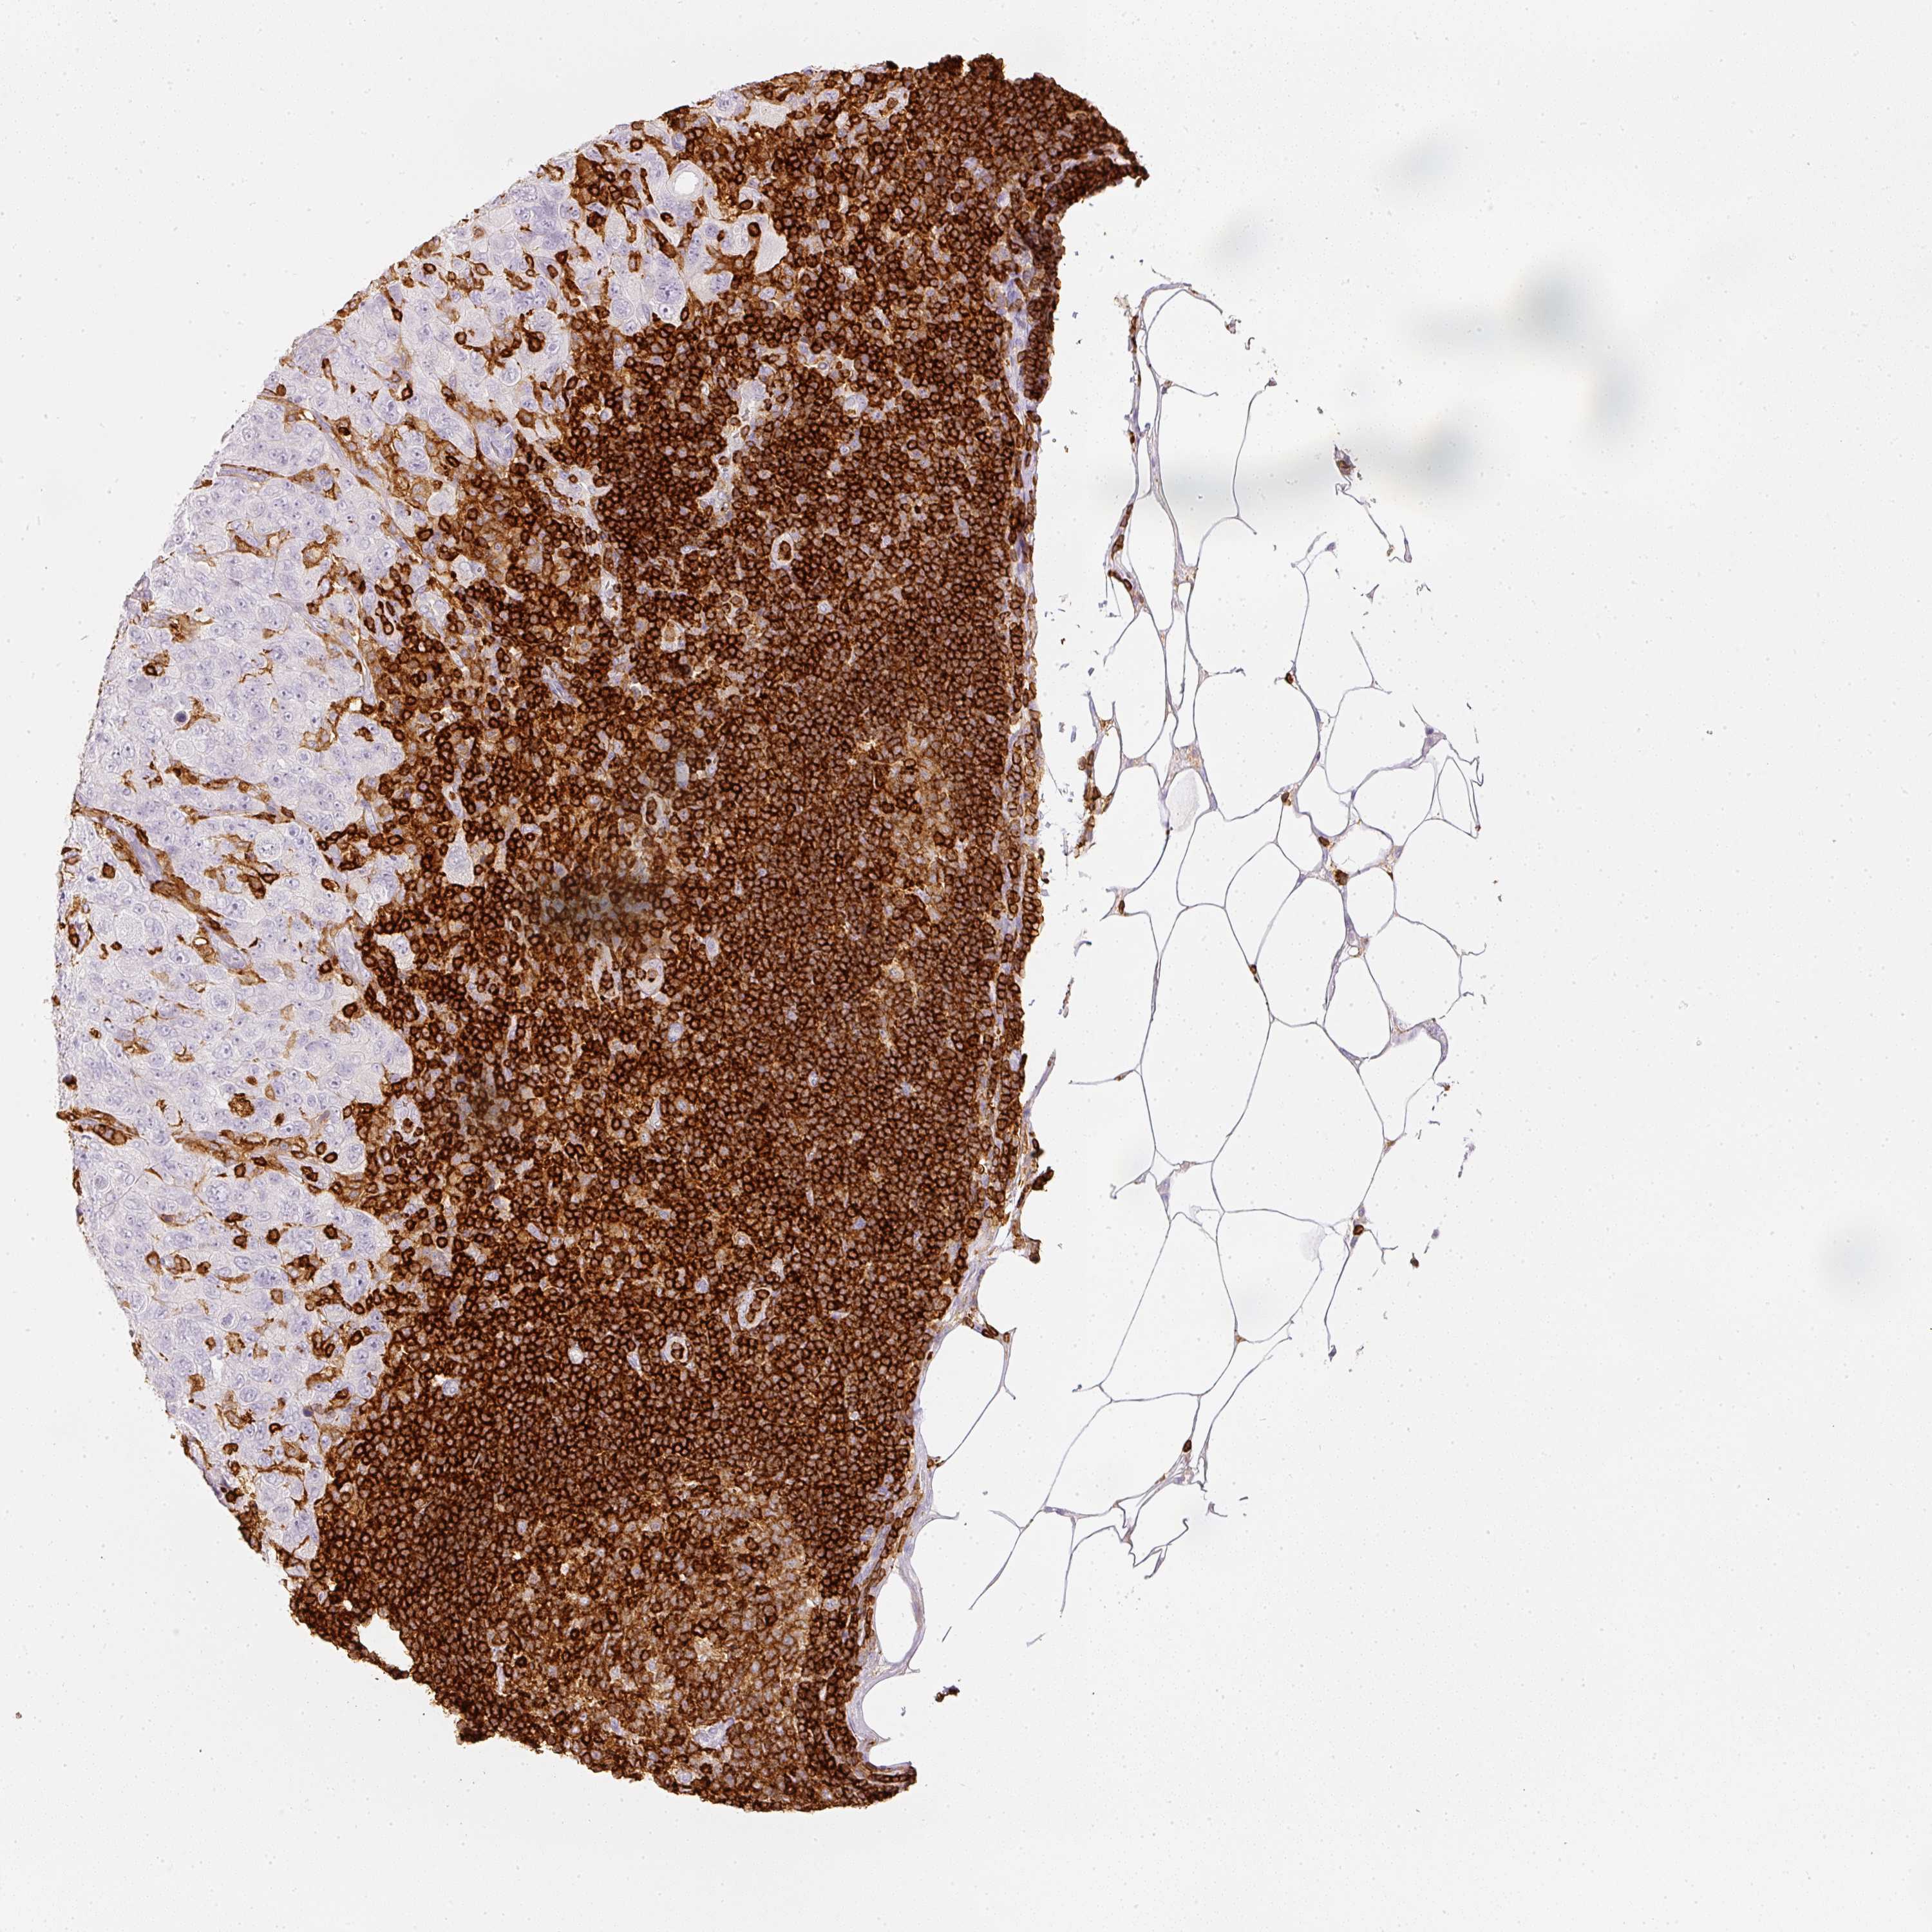

PANCREATIC CANCER - Protein expressioni

A mouse-over function shows sample information and annotation data. Click on an image to view it in a full screen mode. Samples can be filtered based on level of antibody staining by selecting one or several of the following categories: high, medium, low and not detected. The assay and annotation is described here.

Note that samples used for immunohistochemistry by the Human Protein Atlas do not correspond to samples in the TCGA dataset.

Antibody stainingi

Antibody staining in the annotated cell types in the current human tissue is reported as not detected, low, medium, or high, based on conventional immunohistochemistry profiling in selected tissues. This score is based on the combination of the staining intensity and fraction of stained cells.

Each image is clickable and will lead to virtual microscopy that enables deeper exploration of all samples and also displays staining intensity scores, fraction scores and subcellular localization as well as patient and tissue information for each sample.

Antibody HPA018849

Antibody HPA019536

Antibody CAB033987

Staining

High

Medium

Low

Not detected

Intensity

Strong

Moderate

Weak

Negative

Quantity

>75%

75%-25%

<25%

None

Location

Nuclear

Cytoplasmic/membranous

Cytoplasmic/membranous,nuclear

Adenocarcinoma, NOS